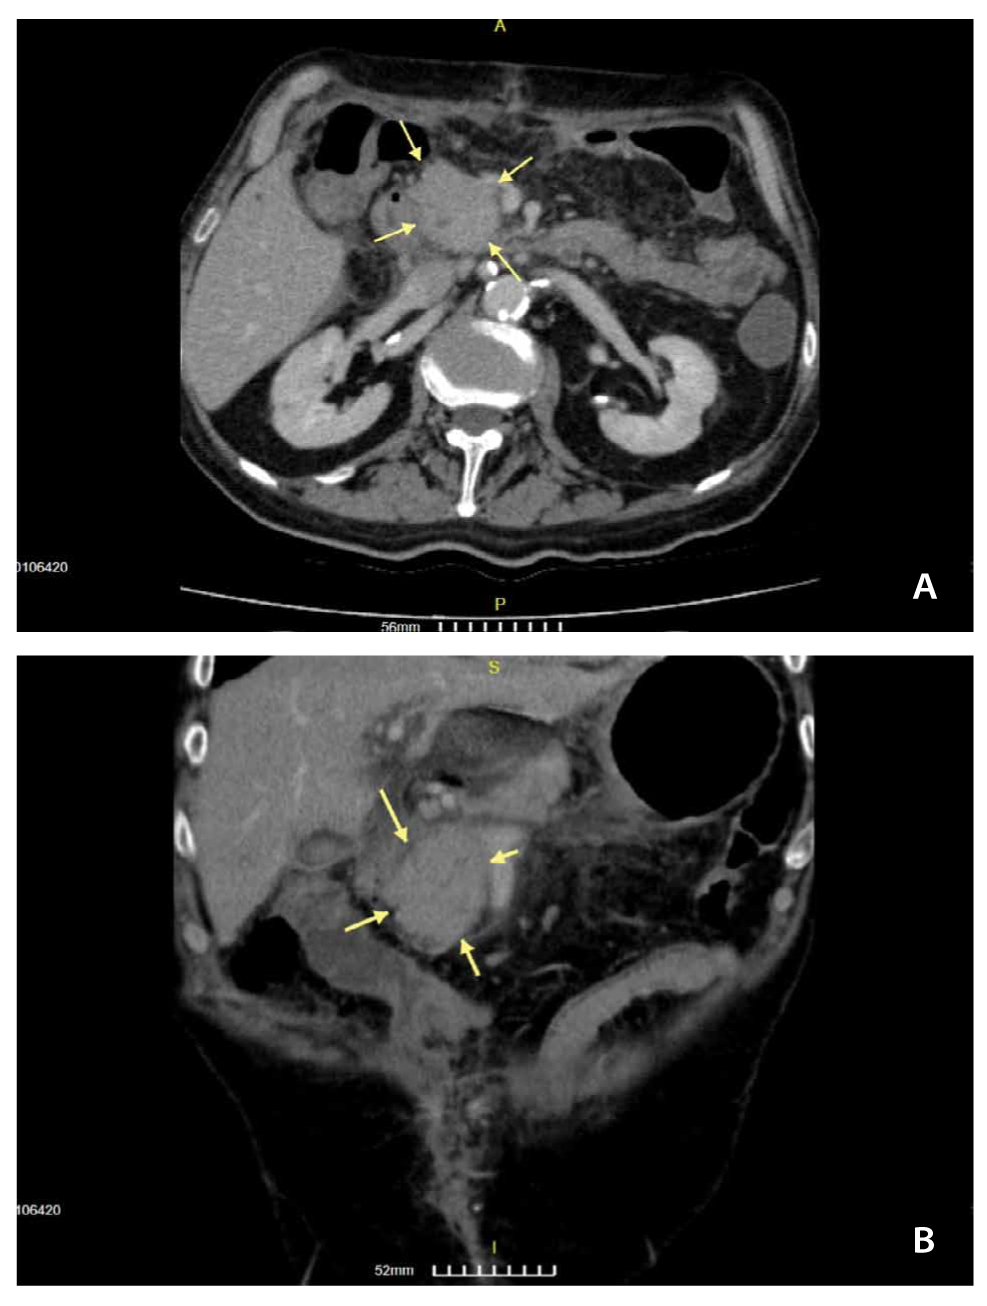

The CT that he brought showed a mass lesion in the head of the pancreas (Figure 1A, 1B) measuring 4.0 x 4.5 x 4.1 cm. No other imaging tests have been performed. The EUS revealed a hypoechogenic compact mass with homogeneous texture and longest diameter approximately 4cm, which did not infiltrate the main pancreatic duct, the common bile duct or important blood vessels. The extra-hepatic bile tree was normal. There were no lymph nodes near the pancreas or hepatic lesions that were suspected of metastasis (at the region that we could examine). EUS-FNB performed through the stomach, with a 22-gauge needle, was performed. Pathology test revealed a rare diagnosis and particularly: necrotic granulomatous inflammation, composed of central necrotic zone surrounded by epithelioid histiocytes with varied numbers of multinucleated giant cells and lymphocytes (Figure 2 and 3). Finally, Ziehl-Neelsen staining revealed the diagnosis of pancreatic tuberculosis (Figure 4A, 4B).

Figure 1. A – B. The yellow arrows show the pancreatic tumor that led the patient to EUS-FNB for the final diagnosis.